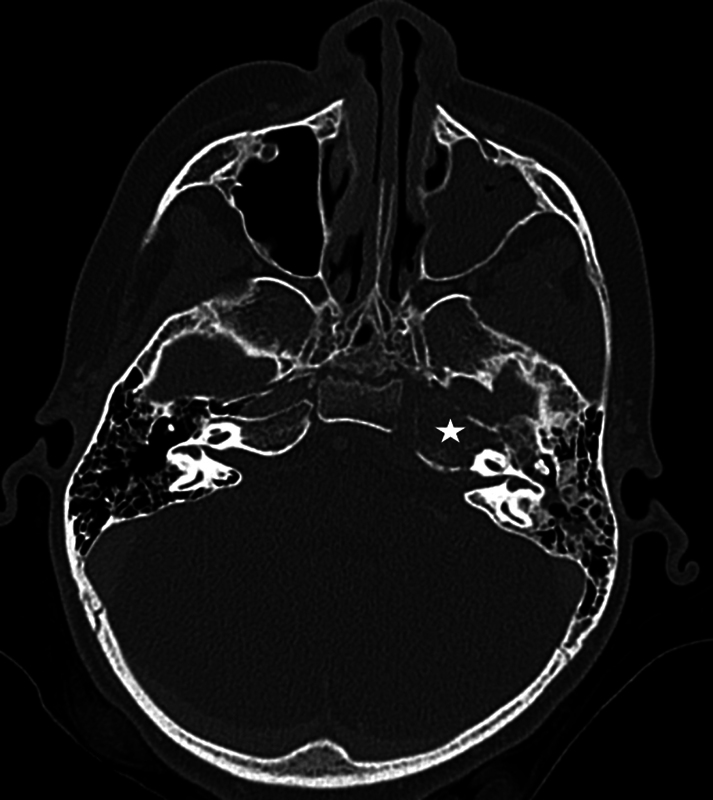

横纹肌肉瘤(Rhabdomyosarcoma, RMS)是一种罕见的恶性肿瘤,每100万儿童中有4.58例发生,约35%发生在头颈部。颅底RMS通常出现在晚期,由于其与其他颅底病理的重叠特征以及难以进入病变进行活检而延误诊断。本病例说明了这些挑战在颅底RMS模拟骨髓炎的岩尖。病例:一名6岁免疫功能正常的女性,有两次急性中耳炎病史,有3周的第6脑神经麻痹史和突然发作的完全性第7脑神经麻痹史。她没有疼痛或耳漏。计算机断层扫描(CT)和磁共振成像显示一个1.3厘米的左岩尖增强病变,延伸到乳突和斜坡,周围的骨和软组织破坏。核医学扫描(锝-99m和镓)显示左侧岩尖摄取旺盛。有效诊断为颅底骨髓炎,为此患者接受了2.5周的抗生素治疗。未能改善后,重复影像学显示疾病明显进展,并扩展到鼻咽和蝶窦。内镜下经蝶窦活检与RMS病理一致。胸部CT示肺转移。患者对用长春新碱、放线菌素- d和环磷酰胺交替使用长春新碱和伊立替康的化疗有部分反应。在化疗的第13周,她接受了总剂量5040 cGyRBE的质子治疗。确诊5个月后,她出现脑膜轻散,并进一步并发脑膜炎,最终去世。

Rhabdomyosarcoma (RMS) is a rare malignant tumor, affecting 4.58 per 1 million children, with approximately 35% occurring in the head and neck. Skull base RMS commonly presents at advanced stages and delays diagnosis due to its overlapping features with other skull base pathology, and difficulty accessing the lesion for biopsy. This case illustrates these challenges in skull base RMS mimicking osteomyelitis of the petrous apex. Case: A 6-year-old immunocompetent female, with a history of two acute otitis media episodes, presented with a 3-week history of sixth cranial nerve palsy and sudden-onset complete seventh cranial nerve palsy. She did not have pain or otorrhea. Computed tomography (CT) and magnetic resonance imaging revealed a 1.3 cm left petrous apex enhancing lesion with extension into the mastoid and clivus with surrounding bony and soft tissue destruction. A nuclear medicine scan (Technetium-99m followed by gallium) demonstrated avid uptake in the left petrous apex. The working diagnosis was skull base osteomyelitis, for which the patient received 2.5 weeks of antibiotics. After failing to improve, repeat imaging showed significant progression of the disease and extension into the nasopharynx and sphenoid sinus. An endoscopic trans-sphenoidal biopsy was performed with pathology consistent with RMS. CT chest revealed lung metastases. The patient partially responded to chemotherapy with vincristine, actinomycin-D, and cyclophosphamide alternating with vincristine and irinotecan. During week 13 of chemotherapy, she received concomitant proton therapy to a total dose of 5040 cGyRBE. Five months after diagnosis, she developed leptomeningeal spread, which was further complicated by meningitis, and passed away.